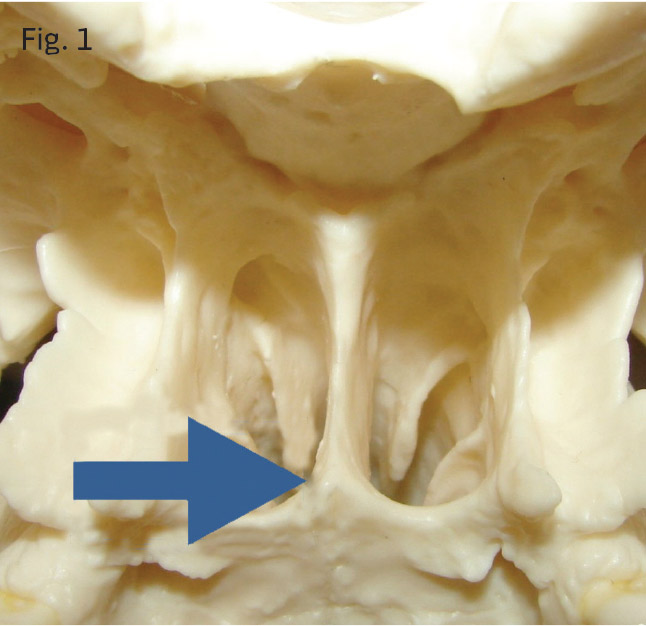

- A miniscrew of inadequate length that didn't puncture the vomer (Fig 1).